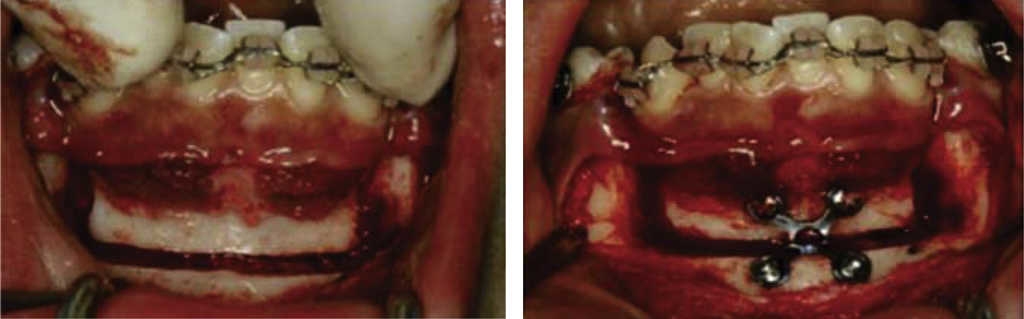

Periodontically accelerated osteogenic orthodontics (PAOO), (Wilcko 2001)

This technique, proposed in 2001 by the orthodontist and periodontist Wilcko brothers is executed in three surgical phases.4

First phase: selective alveolar decortization was conducted, and a total thickness (muco-periosteal) flap was raised.2 Vertical corticotomies were executed in inter-radicular spaces, (vestibular/lingual/palatal) with a number 1 round burr, preserving a distance of 2-3 mm to the osseous crest and exceeding by 2 mm the dental apex.2 According to each case, vertical corticotomies were linked to semi-circular corticotomies in the upper or lower portion of the apex (Figure 8).4 After this, 0.5 mm deep perforations were undertaken on the root of the tooth with a round burr. These perforations were limited to vestibular and lingual cortical bone and had the aim of providing maximum bleeding (Figure 9).4 This technique recommends to locate perforations in the thickest areas of cortical bone, following dental root morphology.4

Figure 8 Link of inter-radicular vertical corticotomies with semi-circular cortcotomies at the apical third.

Second phase: consists on following alveolar increase procedures by placing bone graft material. Decalcified matrixes stimulate osteoblastic activity (Figure 10), thus, after procedure, alveolar volume increase is achieved. Flaps are sutured with 4-0 silk or 5-0 Gortex; sutures are removed 2 or 3 weeks later, depending on post-surgical assessment.4